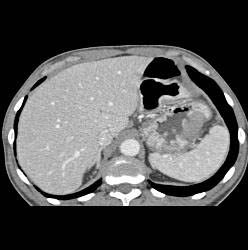

Bulky Tumor C/w Lymphoma Involving Stomach and Kidney